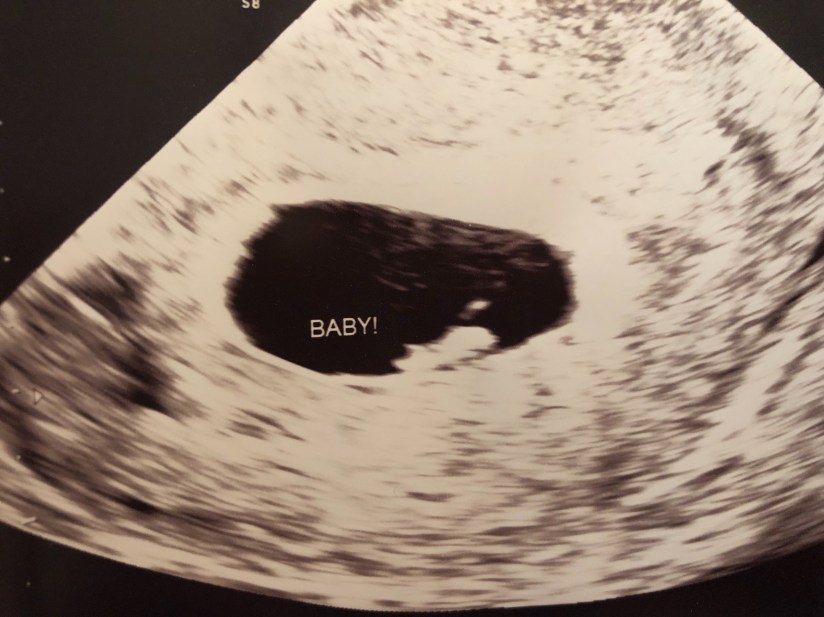

Our first appointment was August 3rd, and we were give a due date of March 21st! We had a solid heartbeat and great check-up with my doctor. We are currently seeing the same doctor I saw through both miscarriages and through Annabelle Grace’s birth! He, like always, was very optimistic and even very open to the idea of me delivering via VBAC (vaginal birth after c-section) assuming both me and the baby were doing well come close to due date. We did get some glamour shots of Baby as well!